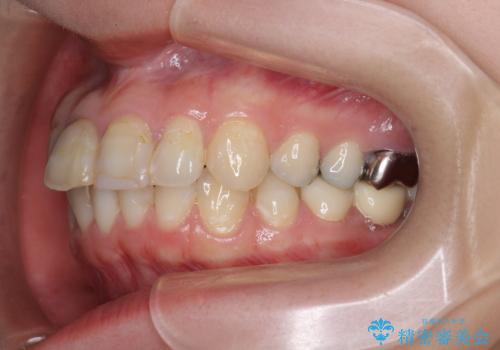

インプラント・セラミック・矯正治療を含む包括歯科診療

- 20代女性

- 矯正装置

- インビザライン

- 治療期間

- 3年

- 治療回数

- 30回以上

- 「地元の歯医者にずっと通っているが、どんどん歯が悪くなる。時間とお金がかかってもいいので徹底的に歯を治したい。」

、と総合的な歯科治療を希望されて来院されました。

虫歯や咬合関係・歯槽骨の吸収・根尖病変・歯の欠損・複合的な問題を一つずつ解決し、

安定した噛み合わせの構築・歯ブラシのしやすい環境の整備・歯内歯周の感染除去・造骨を伴うインプラント治療

を行い、長期的な予後を見込める口腔内環境を確立、整備して行きます。

- 440万円費用は治療当時の料金となります